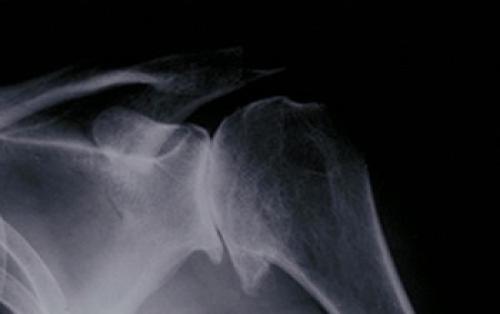

Для точной диагностики артрита плечевого сустава используют методы рентгенографии и компьютерной томографии.